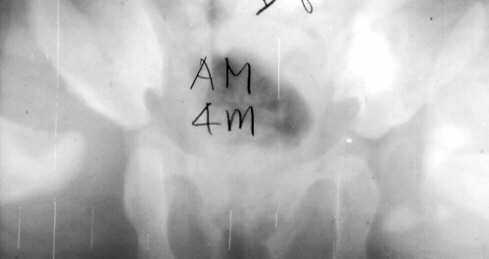

The

damage to the lateral physis may remain dormant until the age

of 10 or 12 years.